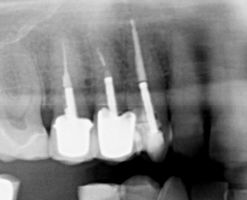

On your initial appointment the dentist will locate the offending tooth and take an x-ray in order to show the roots of the tooth, to see how far the decay has travelled and if there is an abscess present. A course of antibiotics may be given to clear the abscess before the treatment is started as the abscess will reoccur if the treatment is NOT carried out.

• Once access has been gained to the pulp chambers the dead pulp is removed from the root canals using very small files and a hydrochloric wash. An additional x-ray will be taken at this point.

• An X-ray is then taken to check that the canals have been filled completely.